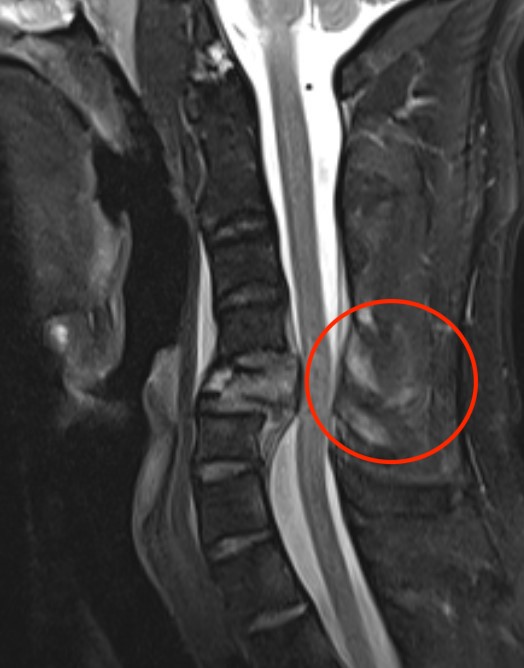

MRI

Assess integrity of posterior column

Evaluate cord injury

MRI images demonstrating spinal cord injury and posterior ligamentous injury